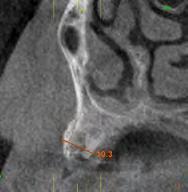

maxilares, lo que apunta a la existencia de una atrofia vertical ósea excesiva en esta área que pretende ser rehabilitada con implantes dentales (Figura 5). A mayor aumento vemos la fractura radicular de la pieza 13 que ha generado el defecto circunferencial (Figura 6) y en el cone beam de planificación se constata y además se pone de manifiesto la dimensión del defecto óseo y el volumen óseo residual a nivel palatino de 2 mm (Figura 7).

Figura 5. Radiografía inicial del paciente. En ella observamos el defecto crateriforme del diente 13 y una neumatización excesiva de ambos senos maxilares en el maxilar posterior donde se pretenden realizar implantes dentales. Figura 6. Imagen en detalle de la pieza 13. En esta imagen cercana podemos observar una fractura vertical evidente en el área del ápice ya en este tipo de prueba radiológica. Figura 7. En el cone-beam de planificación se objetiva la fractura y el defecto crateriforme con pérdida de la tabla vestibular completa y un remanente óseo a nivel palatino de 2 mm para la posterior inserción de un nuevo implante.